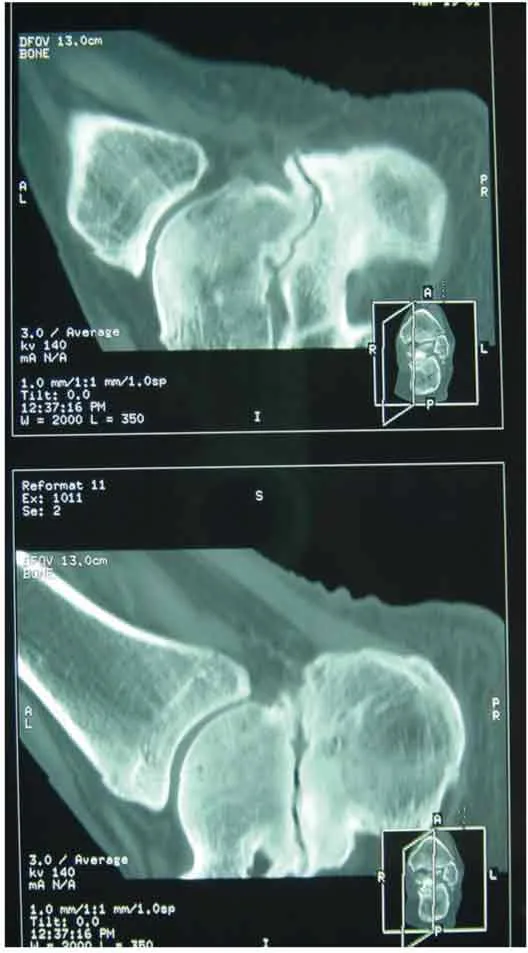

Il s’agit principalement des séquelles des fractures thalamiques du calcanéus (figure 20.9) et du processus latéral du talus et plus rarement de séquelles d’entorses graves péri-taliennes ou d’arthrites ST.L’arthrodèse arthroscopique de l’articulation ST a été initialement décrite par un abord latéral et postéro-latéral [9]. Elle a été ensuite été popularisée par Van Dick [11] qui proposait un abord arthroscopique exclusivement postérieur.Le bilan préopératoire comprend des radiographies de face et de profil en charge de la cheville. Un examen TDM peut être utile pour prévoir la difficulté d’accès à l’articulation ST postérieure (figure 20.10).

arthrodese 30

arthrodese 32